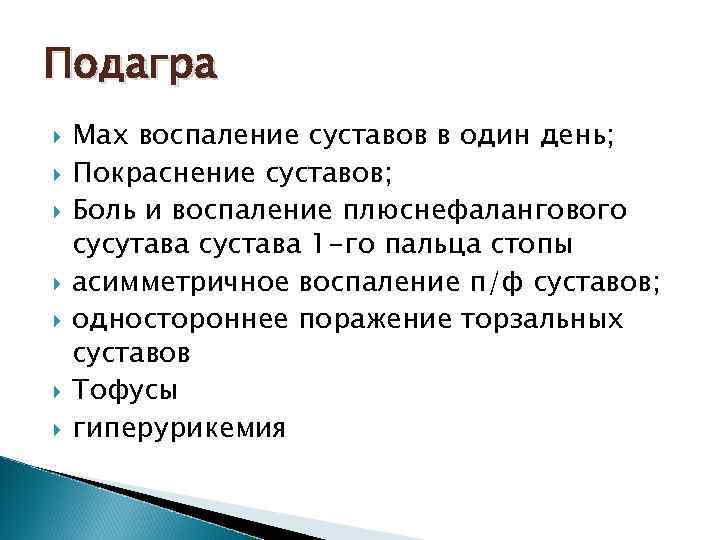

Подагра Max воспаление суставов в один день; Покраснение суставов; Боль и воспаление плюснефалангового сусутава сустава 1 -го пальца стопы асимметричное воспаление п/ф суставов; одностороннее поражение торзальных суставов Тофусы гиперурикемия